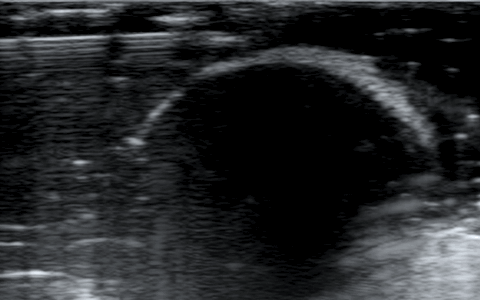

2) Το βάθος (depth), δηλαδή το να φέρουμε στην οθόνη του υπερήχου όσο το δυνατόν πιο κοντά το αντικείμενό μας, ώστε να καλύπτει σχεδόν τα 2/3 της οθόνης μας.

Μειώνουμε το βάθος ώστε να φέρουμε κοντά μας το αντικείμενο.

4) Το focus, δηλαδή την εστίαση της δέσμης, όσο πιο κοντά βρίσκεται σε αυτό που θέλουμε να μελετήσουμε τόσο καλύτερη εικόνα έχουμε.